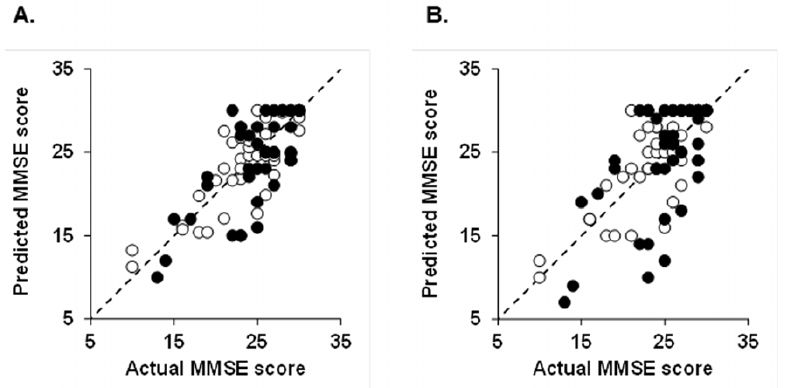

Suzuki M, Sugimura Y, Yamada S, Omori Y, Miyamoto M, Yamamoto J. (2012) Predicting recovery of cognitive function soon after stroke: differential modeling of logarithmic and linear regression.PLoS One. 2013;8(1):e53488. doi: 10.1371/journal.pone.0053488. Epub 2013 Jan 11.